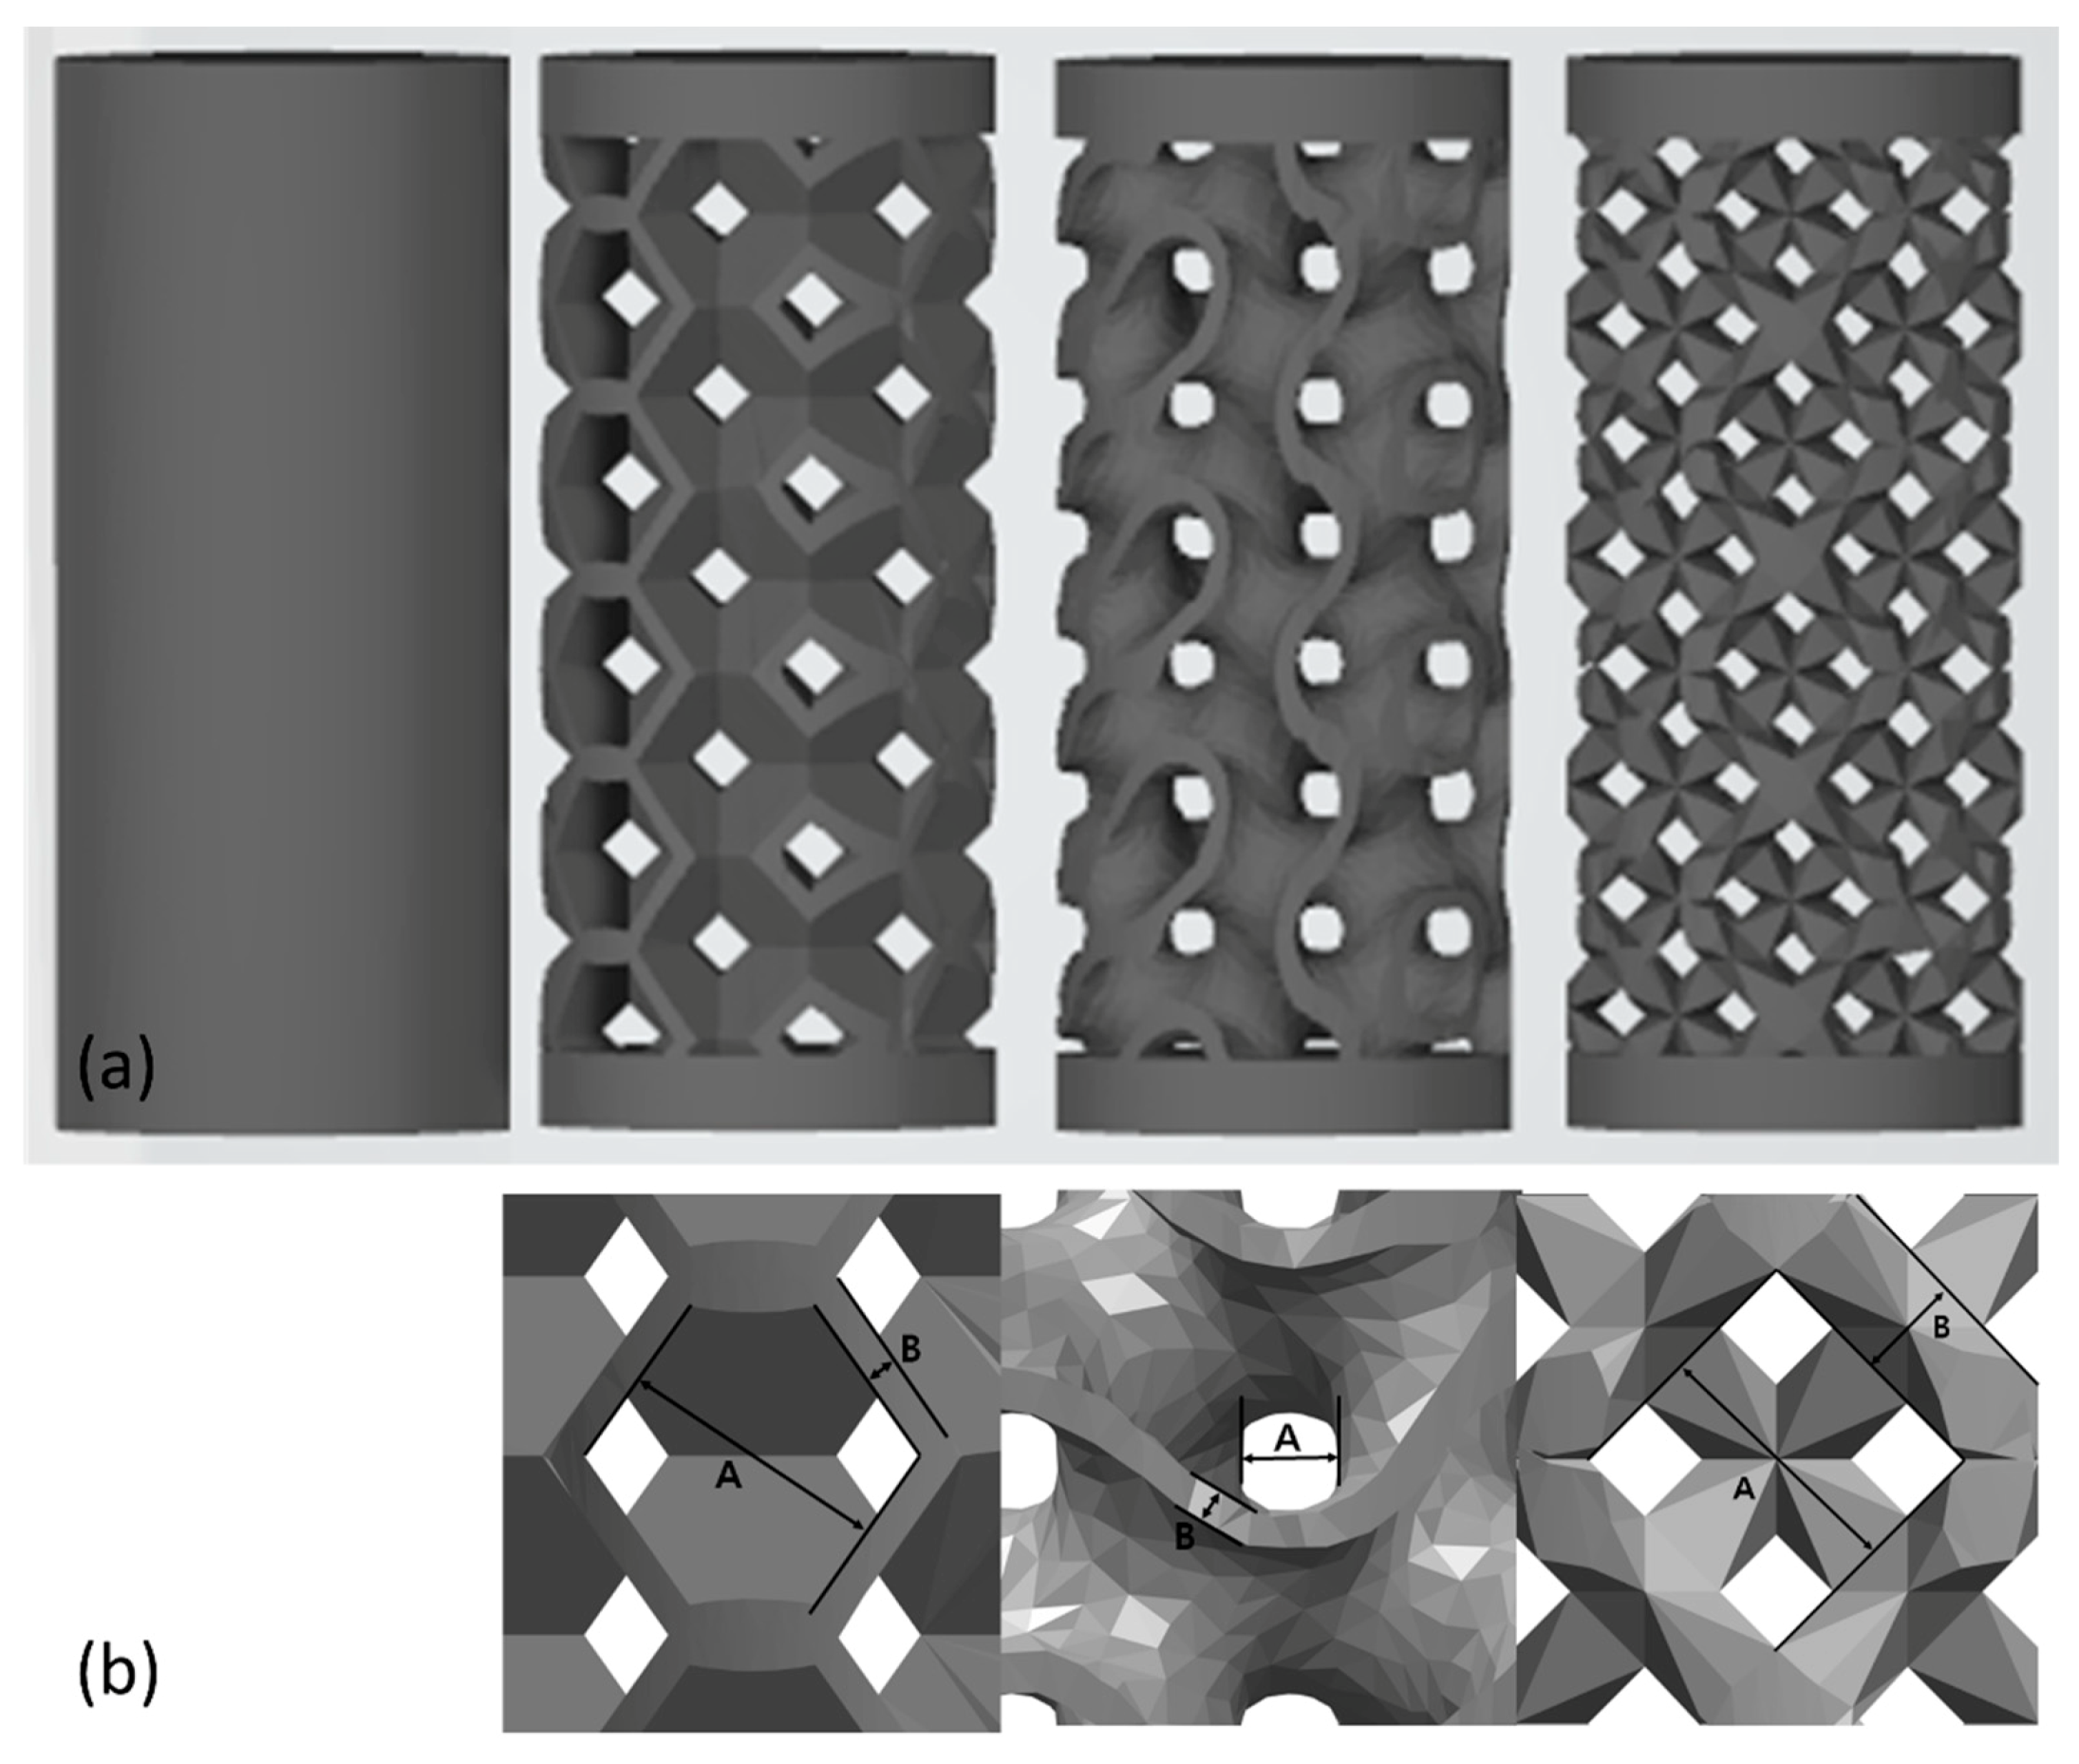

2.1. Selection of the Pore Design